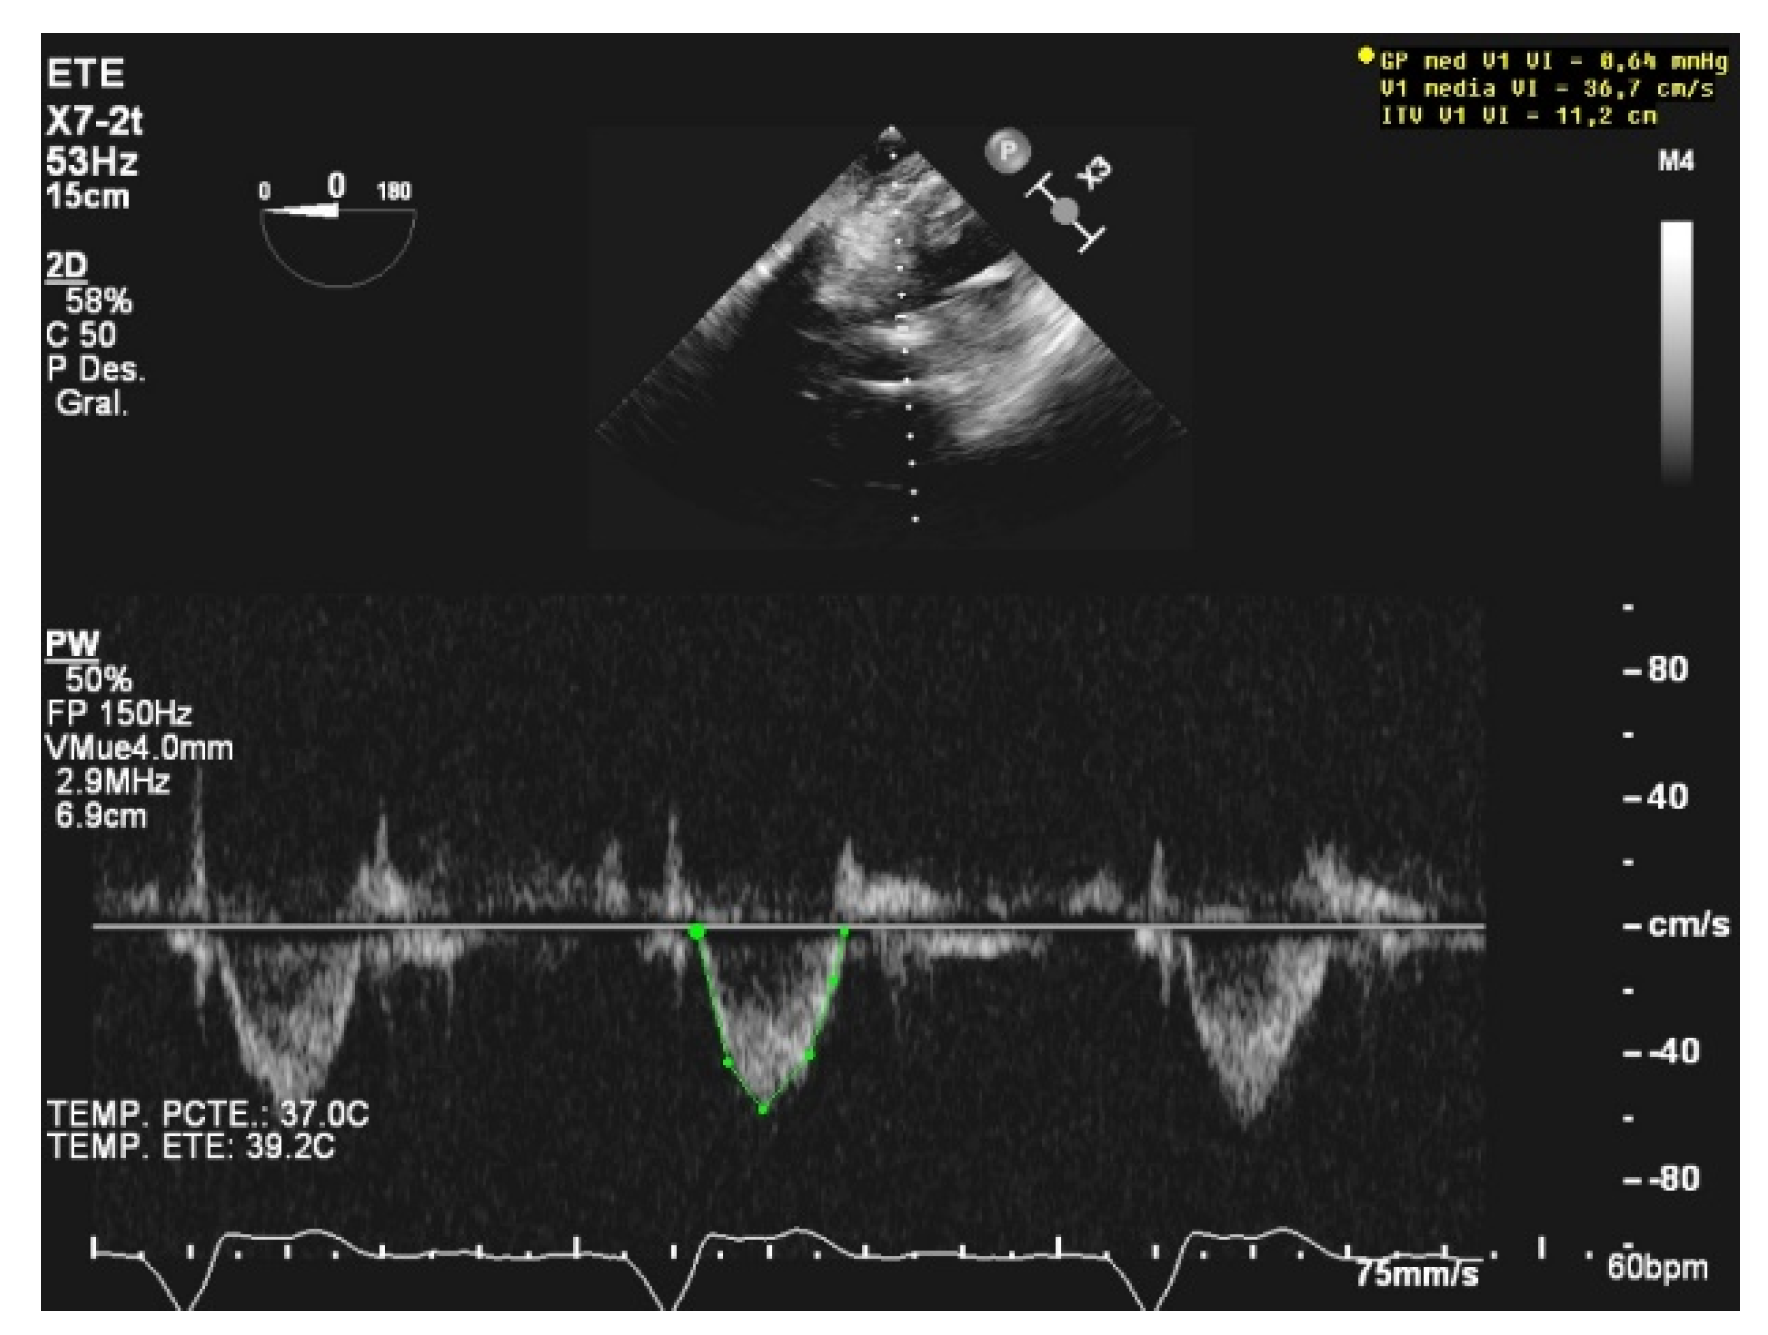

When assessing diastolic function, obtaining an E/e’ mitral ratio higher than 14.5 is associated with higher rates of weaning failure, even in atrial fibrillation [13,19,20], as are E waves higher than 0.87 m/s [13,21] (Figure 1). However, this method is less reliable in acute decompensated heart failure and left ventricles with larger volumes, where significant mitral regurgitation can lead to underestimation, as well as in resynchronization therapy and wide QRS and the subsequent change in septal e’ due to its abnormal motion [22,23].

Figure 1.

E wave height, deceleration time, and A wave. Normal filling pattern.